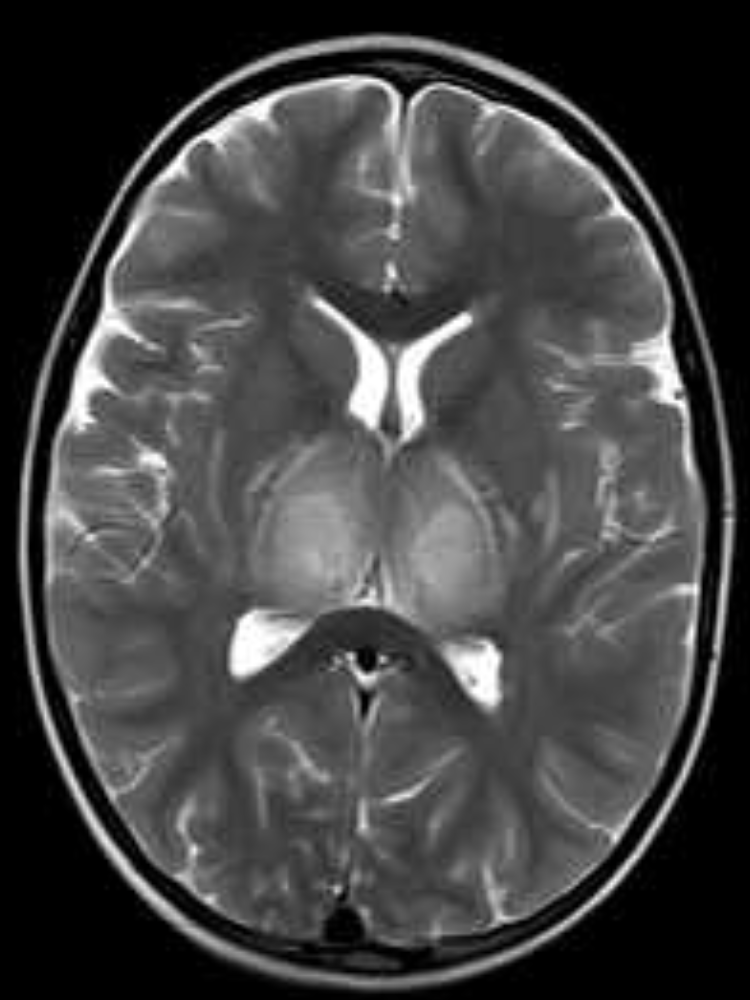

Background

This study explored whether Myelin Water Imaging could detect myelin injury in Anti-NMDA receptor autoimmune encephalitis (NMDAr-AIE), where traditional neuroimaging is often normal. Myelin Water Fraction (MWF) quantifies myelin content by distinguishing myelin sheath water from other brain water compartments.

Methods

Adult participants with confirmed NMDAr-AIE diagnoses and healthy controls (HC) underwent 3T brain MRI (Magnetic Resonance Imaging) including MWF mapping. Participants were recruited after discharge from the hospital. Mean MWF was calculated for 4 white matter regions of interest (ROI). MHI (Myelin heterogeneity Index) was calculated by dividing the MWF standard deviation by the mean MWF. Patient demographics, clinical assessments, treatment, and outcomes were collected.

Results

Five participants with NMDAr-AIE (4F/1M, mean age 30, SD 7) and four HC (3F/1M, mean age 36, SD 6) were included. All NMDAr-AIE participants had normal or non-specific T2 hyperintensities on initial imaging and had received immunotherapy. The mean Modified Rankin Score (MRS) on discharge was 2. MWF (mean ± SD) for normal-appearing white matter, corpus callosum, corticospinal tract, and superior longitudinal fasciculus were 0.10±0.02, 0.12±0.02, 0.15±0.03, 0.12±0.02, which were very similar to HC at 0.09±0.02, 0.11±0.01, 0.15±0.02, and 0.11±0.02, respectively.

Fig. 1 Myelin Water Imaging of two selected patients

Screenshot 2025 06 01 at 12.05.23 pm

Conclusions and Future Direction

Myelin Water Imaging showed no myelin pathology in five NMDAr-AIE patients, with MWF and MHI values comparable to HC, suggesting that myelin pathways are relatively preserved post-recovery from AIE. Moving forward, we aim to continue recruiting healthy controls, patients post-recovery and those experiencing active disease to determine if there are any MWF abnormalities throughout the disease course. Future studies are needed to assess MWF changes in other antibody-mediated encephalitides.